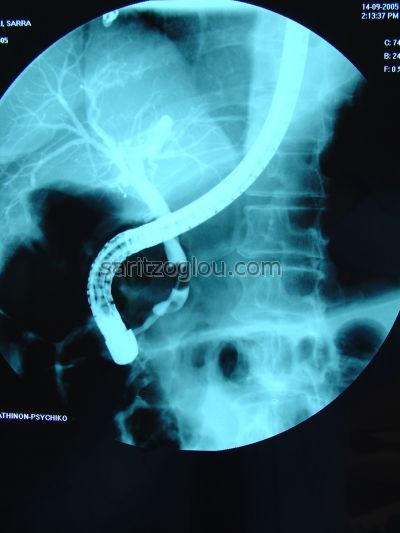

Μετά λαπαροσκοπική χολοκυστεκτομή διαπιστώθηκε λιθίαση χοληδόχου πόρου. Αφαίρεση του λίθου με καθετήρα μπαλόνι. Αναγνωρίζονται το λαπαροσκοπικά clips στον κυστικό πόρο και στην μεσαία εικόνα ο λίθος αμέσως κάτω από το ενδοσκόπιο.

Παρουσία τριών λίθων στο τελικό άκρο του χοληδόχου πόρου. Είχε προηγηθεί λαπαροσκοπική χολοκυστεκτομή. Αφαίρεση των λίθων με καθετήρα μπαλόνι.

Απεικονίζεται ο καθετήρας μπαλόνι με φουσκωμένο το τελικό του άκρο και κάτω από αυτόν μικρός λίθος στο τελικό άκρο του χοληδόχου πόρου